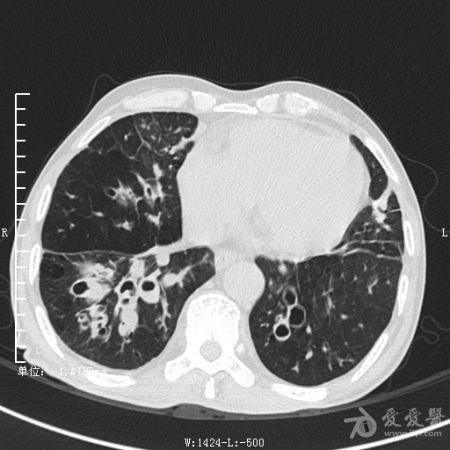

典型支气管扩张及肺水肿CT片

典型支气管扩张肺水肿